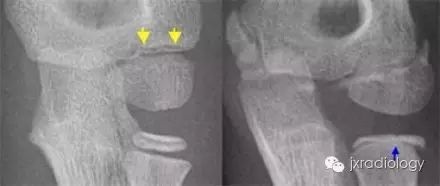

病例图片:骨骺裂

黄箭骨折;蓝箭是骨骺裂。LEFT a subtle lateral condyle fracture. Less than 2 mm displacement and probably stable. RIGHT a different case. Oblique view gives nice impression of fracture. Blue arrow indicates a cleft epiphysis of the radius (normal variant)